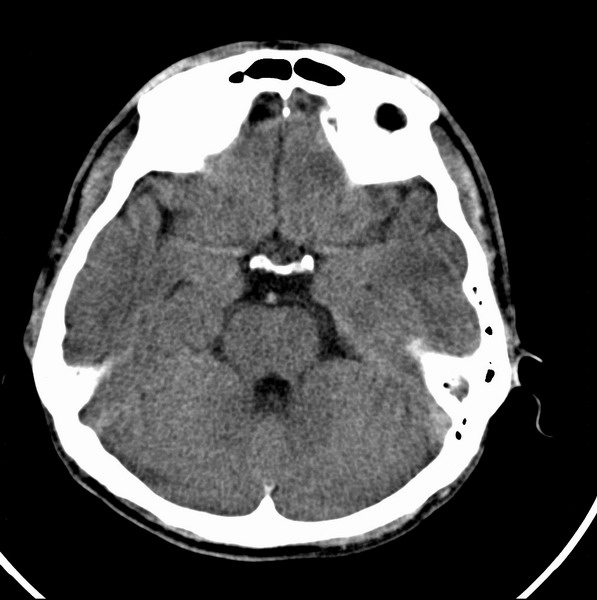

标题: CT21509:额叶低密度影

男、29

突发痴呆,失语,记忆减退,反应迟钝二十小时。

右侧额叶低密度影,边界清晰,无占位效应,符合:额叶皮质脑软化灶。

双额叶脑沟增深增宽,皮质性脑萎缩可以考虑么?

左额叶也有类圆形低密度影,同右侧低密度灶近颅底一层同层,病灶周脑实质密度似稍高,成环状,这个没有问题么?

考虑右侧额叶脑软化灶;建议必要时行mri检查排除其他。

考虑皮质软化灶。不考虑胶质瘤,是因为胶质瘤一般发生于白质内。